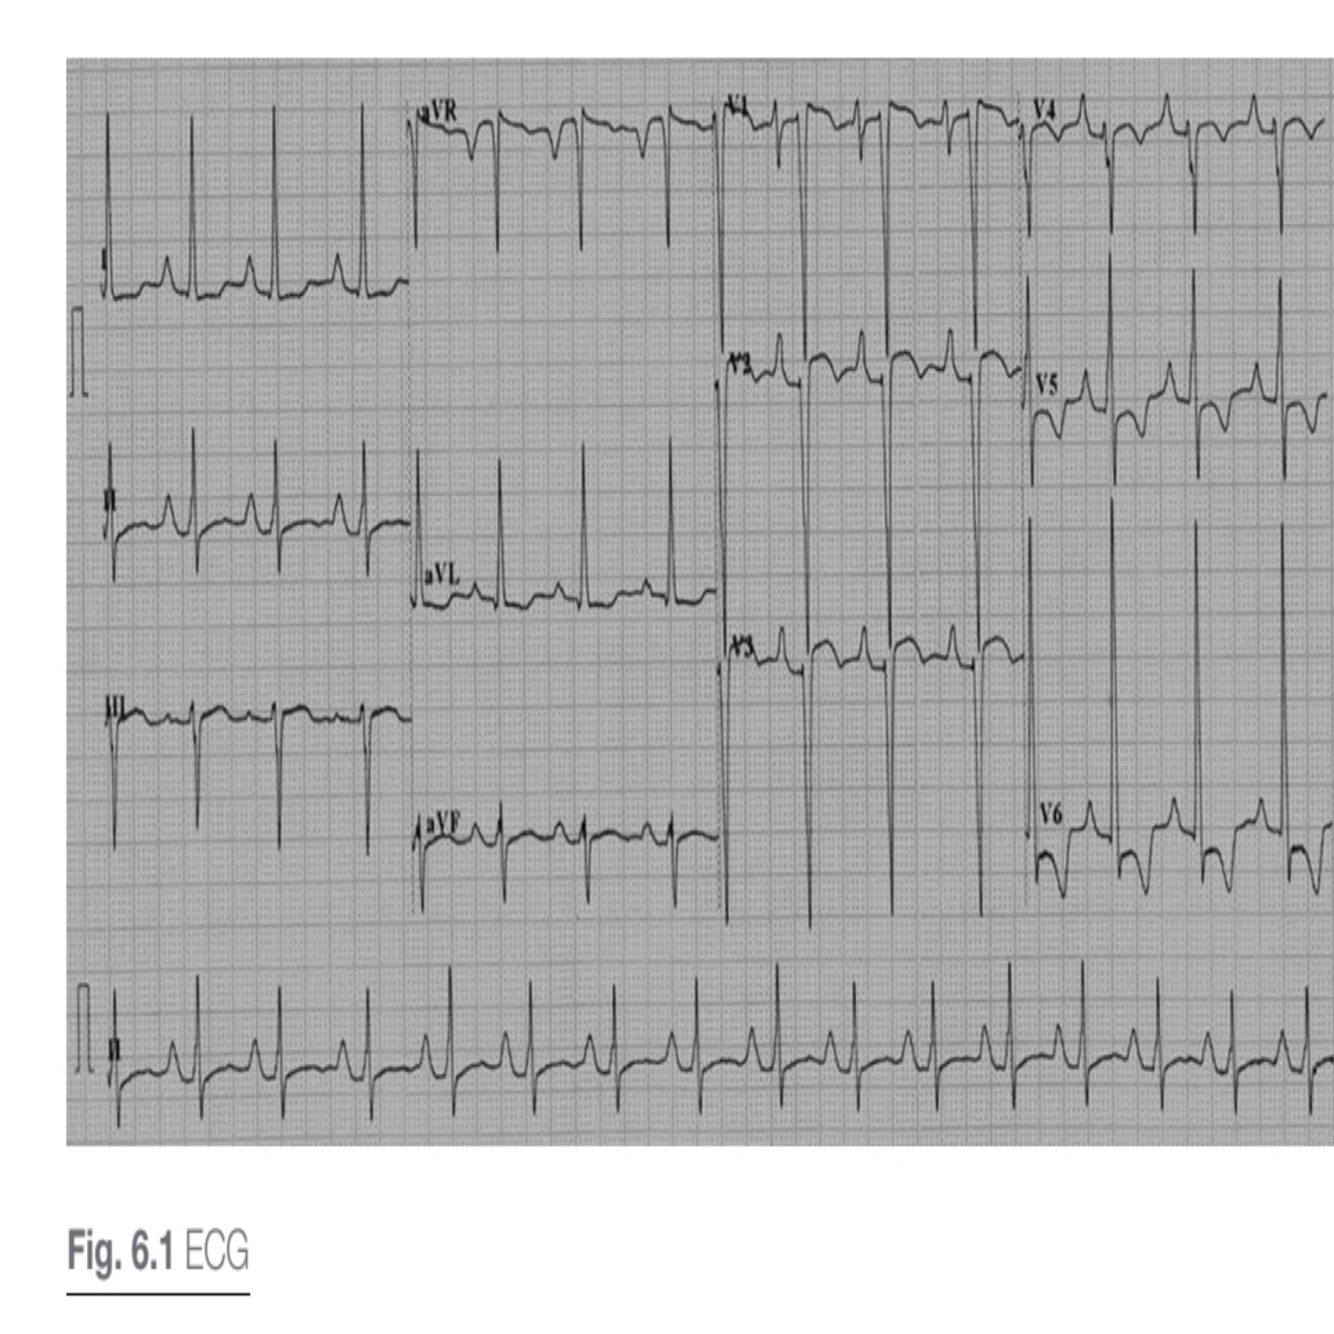

Describe the ecG.

Interpretation:

• Voltage criteria for LVH

• Diffuse ST segment and T wave changes, indicating strain